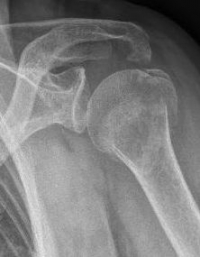

Picture: A subcapital upper arm fracture was treated with a prosthesis. The humeral head was completely removed and replaced by the prosthesis. This is anchored in the upper arm with the prosthesis shaft.